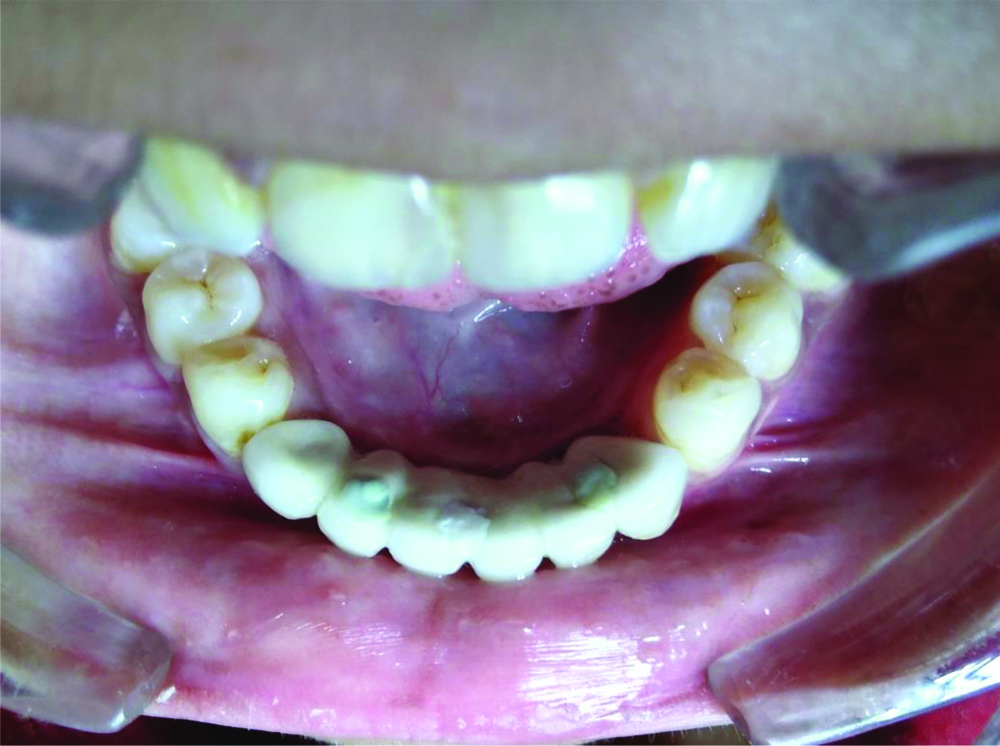

A 13-year-old female patient reported to the Department of Pedodontics and Preventive Dentistry, with the complaint of poor aesthetics, missing lower front teeth and difficulty in speech due to restriction of tongue movements. Parents also informed about her low self-esteem. On oral examination all permanent mandibular anterior teeth including central and lateral incisors and canines (31,32,33,41,42,43) were missing. Ankyloglossia was also noted [Table/Fig-1].

Preoperative photograph showing missing lower anterior teeth and Ankyloglossia (Heart shaped tongue tip).